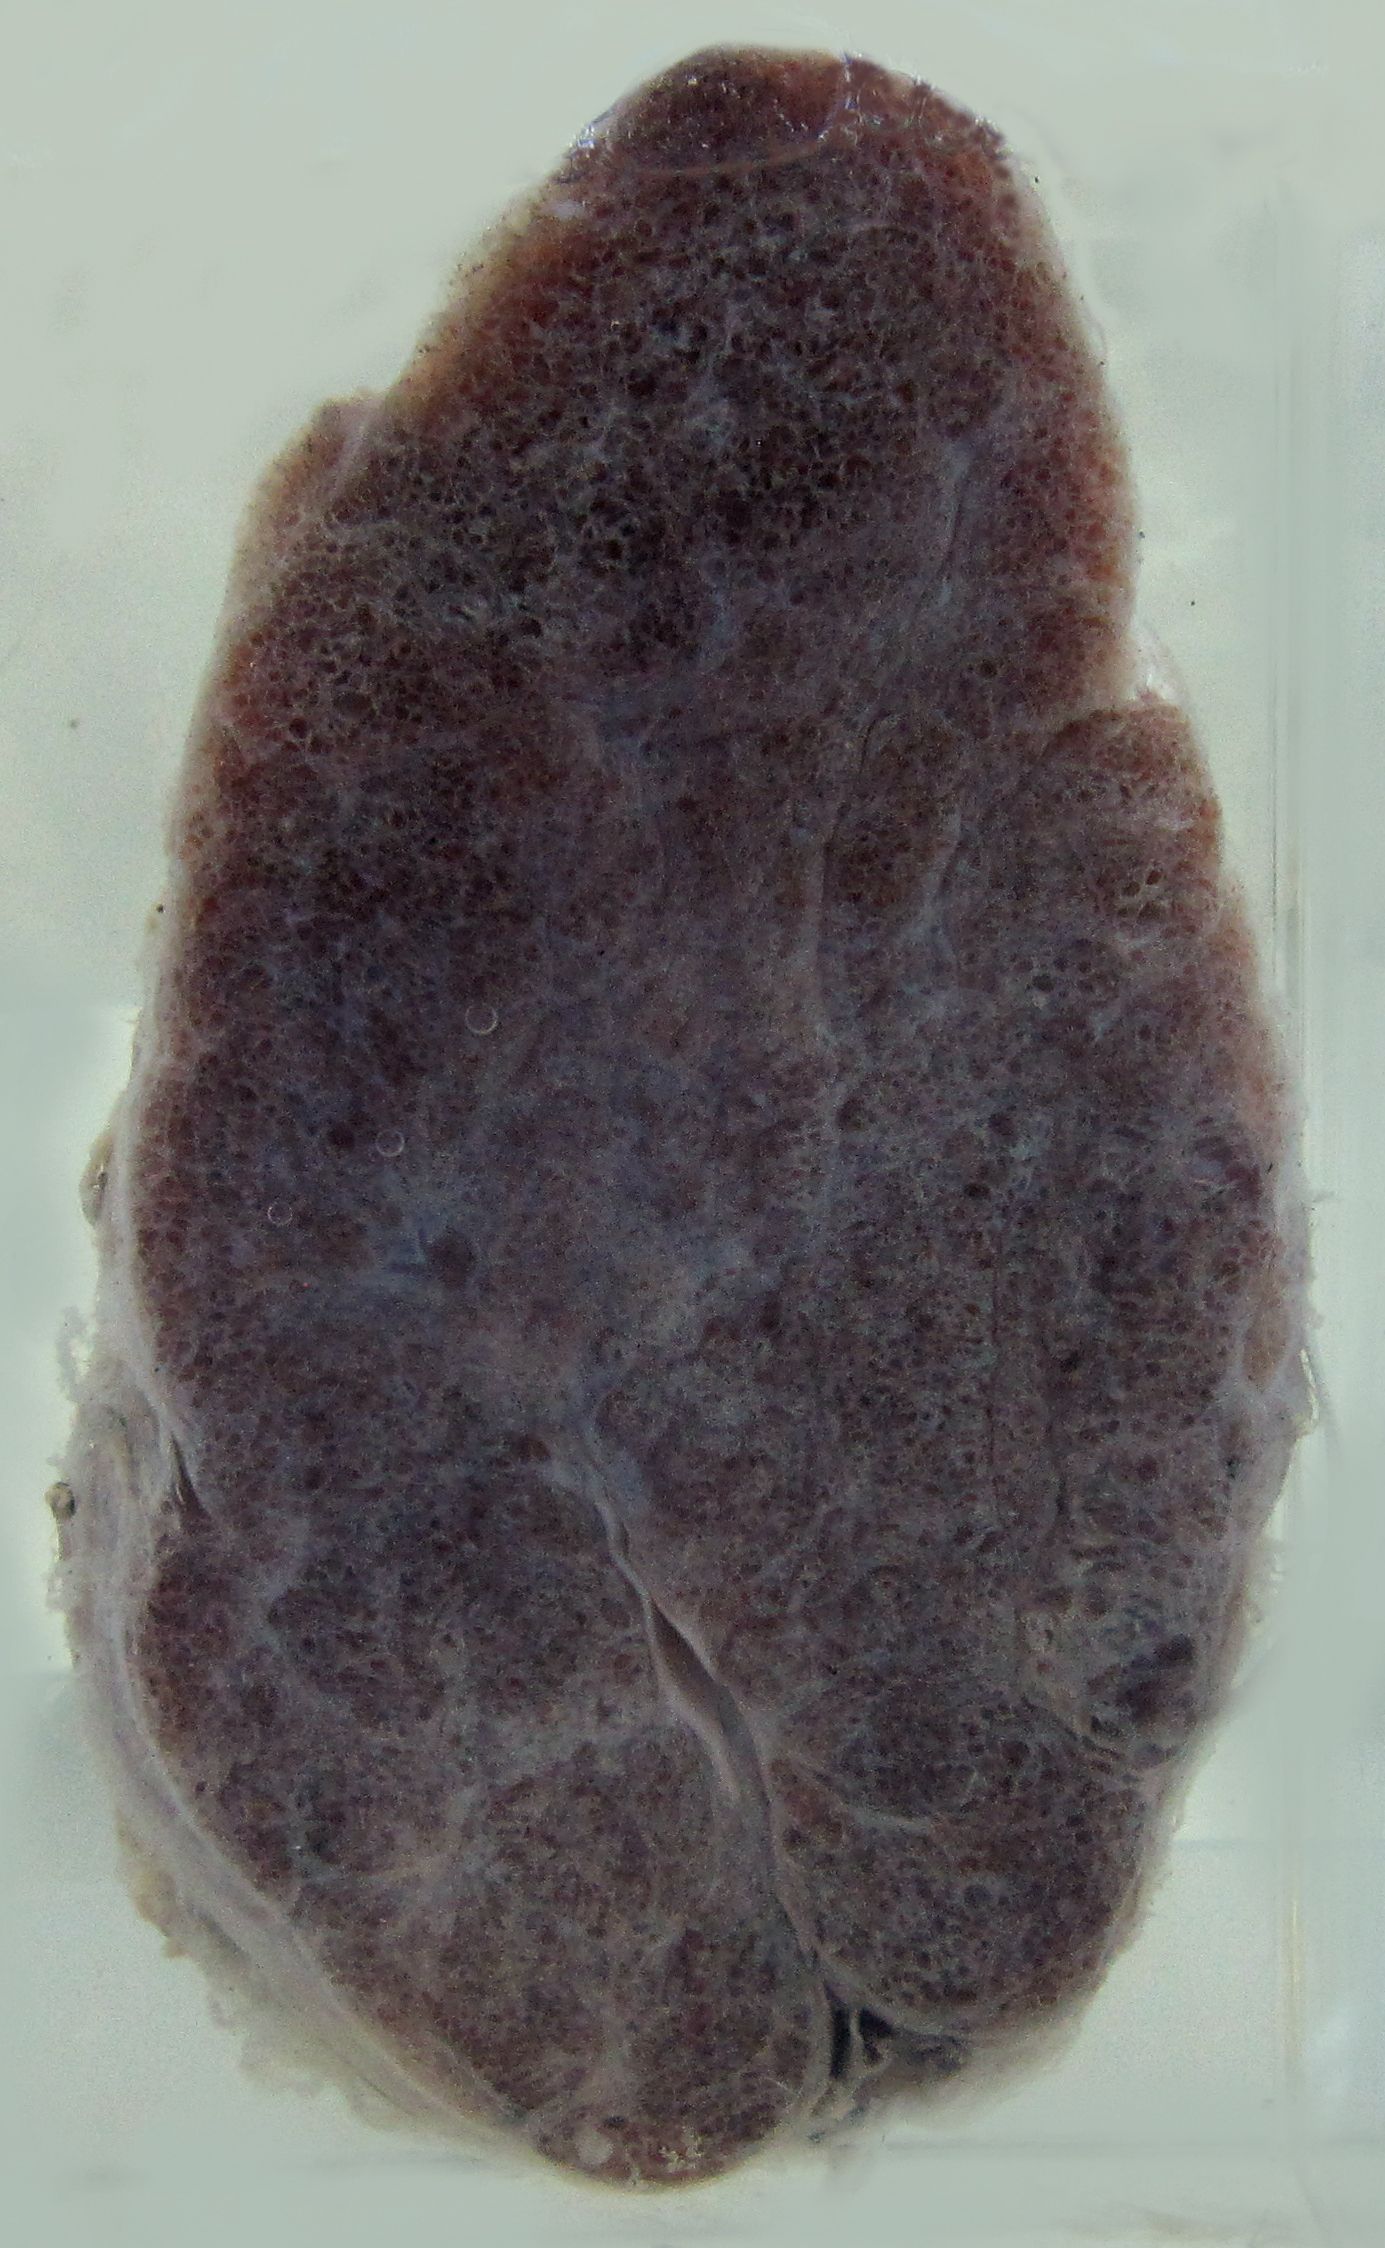

1.胶性甲状腺肿